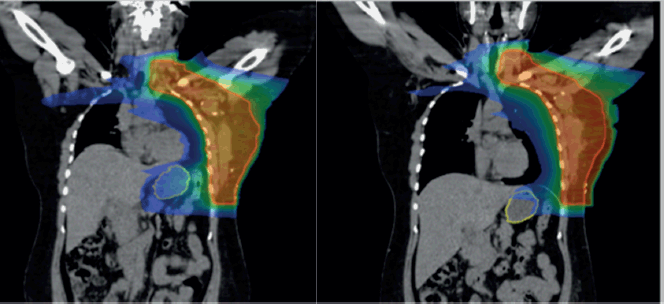

Overall, the significant factors influencing acute upper GI toxicity included radiation technique, RT dose and dose to stomach (D10 cc, D30 cc and D60 cc). Importantly, left chest wall or breast irradiation with or without RNI during FB was associated with a significantly higher risk of GI toxicity compared to DIBH, which holds a significant negative correlation implying a protective effect and helps in reducing GI toxicity (p = 0.035) (Supplementary

Figures 1a,b and 2a,b). Additionally, a positive correlation was found between larger PTV volume and the risk of developing acute upper GI toxicity (p = 0.036).

The Mann-Whitney U test was used to compare stomach dose parameters (D10, D30 and D60 cc) between FB and DIBH. Stomach D10 cc, the higher-dose region most closely associated with acute toxicity, showed no significant difference between FB and DIBH (Mann-Whitney U = 898.500, Z = −1.712, p = 0.087). This suggests that DIBH helps control the dose to critical stomach sub-volumes, potentially reducing the risk of upper GI toxicity. Interestingly, D30 and D60 cc doses were higher in the DIBH group (p = 0.013 and p = 0.002, respectively). However, these differences are likely to reflect anatomical and positional variations associated with breath-hold techniques rather than an increased clinical risk. Clinical correlation with upper GI toxicity indicated a protective trend for DIBH, reinforcing its role in mitigating toxicity by improving treatment reproducibility and reducing motion-related dose variability (Supplementary Figure 2a and b).

Supplementary Figure 2. (a): Coronal view showing stomach position in FB (VMAT), (b): In DIBH (VMAT).